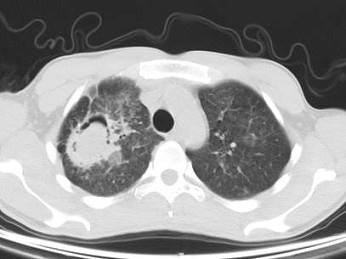

问题 男,32岁,咯血,咳痰一周,胸部CT如图,最可能的诊断为 ( )

选项 A、右上肺结核性空洞并霉菌感染 B、组织胞浆菌病 C、周围型肺癌 D、右上肺感染 E、肺结核

答案 A